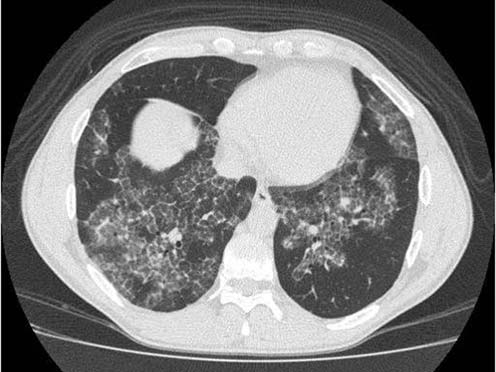

Рис. 3. Фрагмент компьютерной томограммы больного альвеолярным протеинозом.

Участки "матового стекла", отграниченные от неизмененных участков. Утолщение междольковых перегородок в зонах "матового стекла".

Подробнее следует остановиться на характерных симптомах альвеолярного протеиноза выявляемых при компьютерной томографии высоких разрешений (рис. 2, 3):

- Наличие зон «матового стекла»:

- всегда одновременно в обоих легких

- достаточно четко отграничены от неизмененной паренхимы, что придает им «географический вид», могут иметь очень четкие контуры в случае прилежания к плевре междолевых щелей

- нет четкой анатомической привязки

- процесс может быть фокальным («пятнистым») или распространенным.

- Утолщение междольковых перегородок:

- только в зонах «матового стекла»

- характерный вид «булыжной мостовой» ("crazy paving"). В основе симптома - утолщение междольковых перегородок, обусловленное отеком и неравномерной лимфоцитарномакрофагальной инфильтрацией [4].